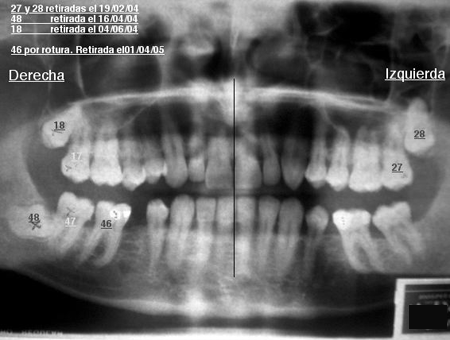

Algunos ejemplos de imágenes digitales

Pulse en las imágenes para ver la ampliación

anciano-fte

dientes